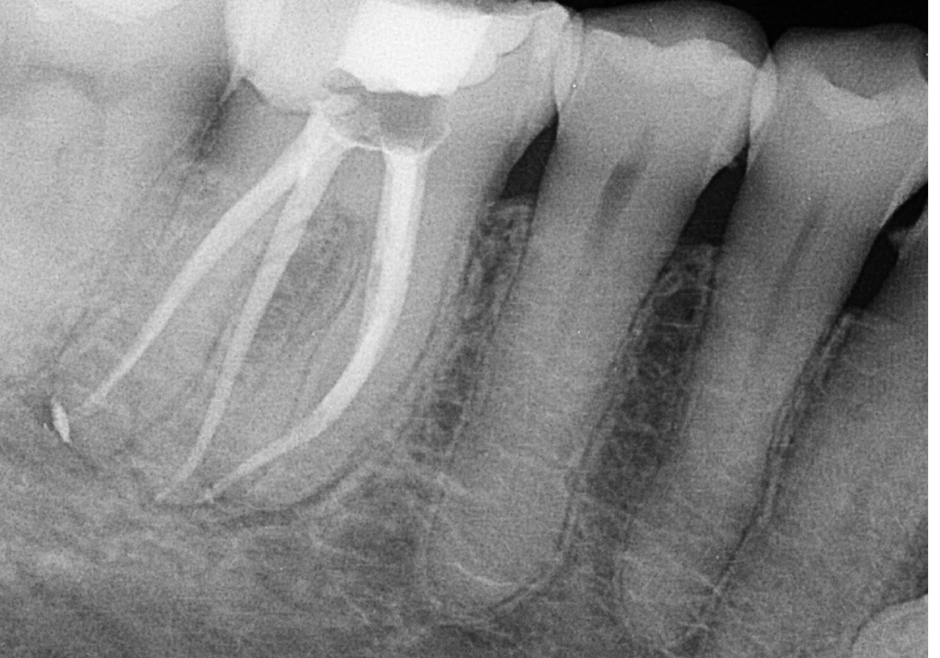

Case Study by Dr. Randy Cross

EndoScore of 3 at finish. Necrotic Symptomatic Apical Periodontitis. 2 visit with triple antibiotic paste, 30x06 conserve file with matching GP and Endoceramic sealer. Finished with bonded VistaApex clear flowable. The patient is being recalled in one year to confirm healing.

EndoScore: 3